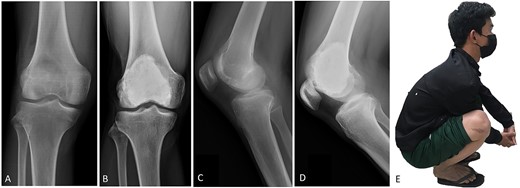

(A, C) Case no. 7: female, 54 years of age with GCTB at the proximal tibia with subchondral bone involvement, Campanacci grade III. (B, D) Radiograph at 58 months after extended curettage with hydrogen peroxide, phenol, and cementation. (E) MSTS score 86%.